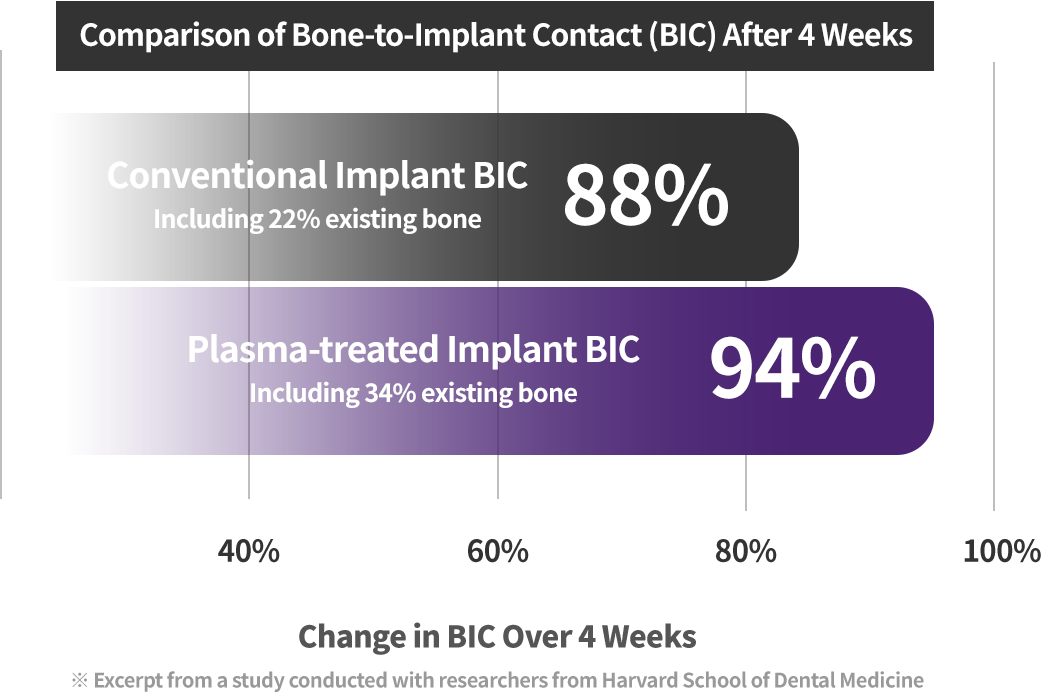

Clinical Results of Plasma Implants

1.7x Higher Bone Integration

Compared with conventional implants, plasma implants showed about 1.7 times higher bone integration within 4 weeks. (Based on 4-week follow-up of actual patients)

94% Bone Integration in Just 4 Weeks

With faster osseointegration, a 94% bone integration rate was reported in a short period. (Based on a publication involving Harvard researchers)

Harvard dental research confirms

the excellent performance of plasma implants

According to research by Harvard School of Dental Medicine, plasma implants showed excellent bone integration, reduced bone loss, shorter healing time, and improved long-term stability.